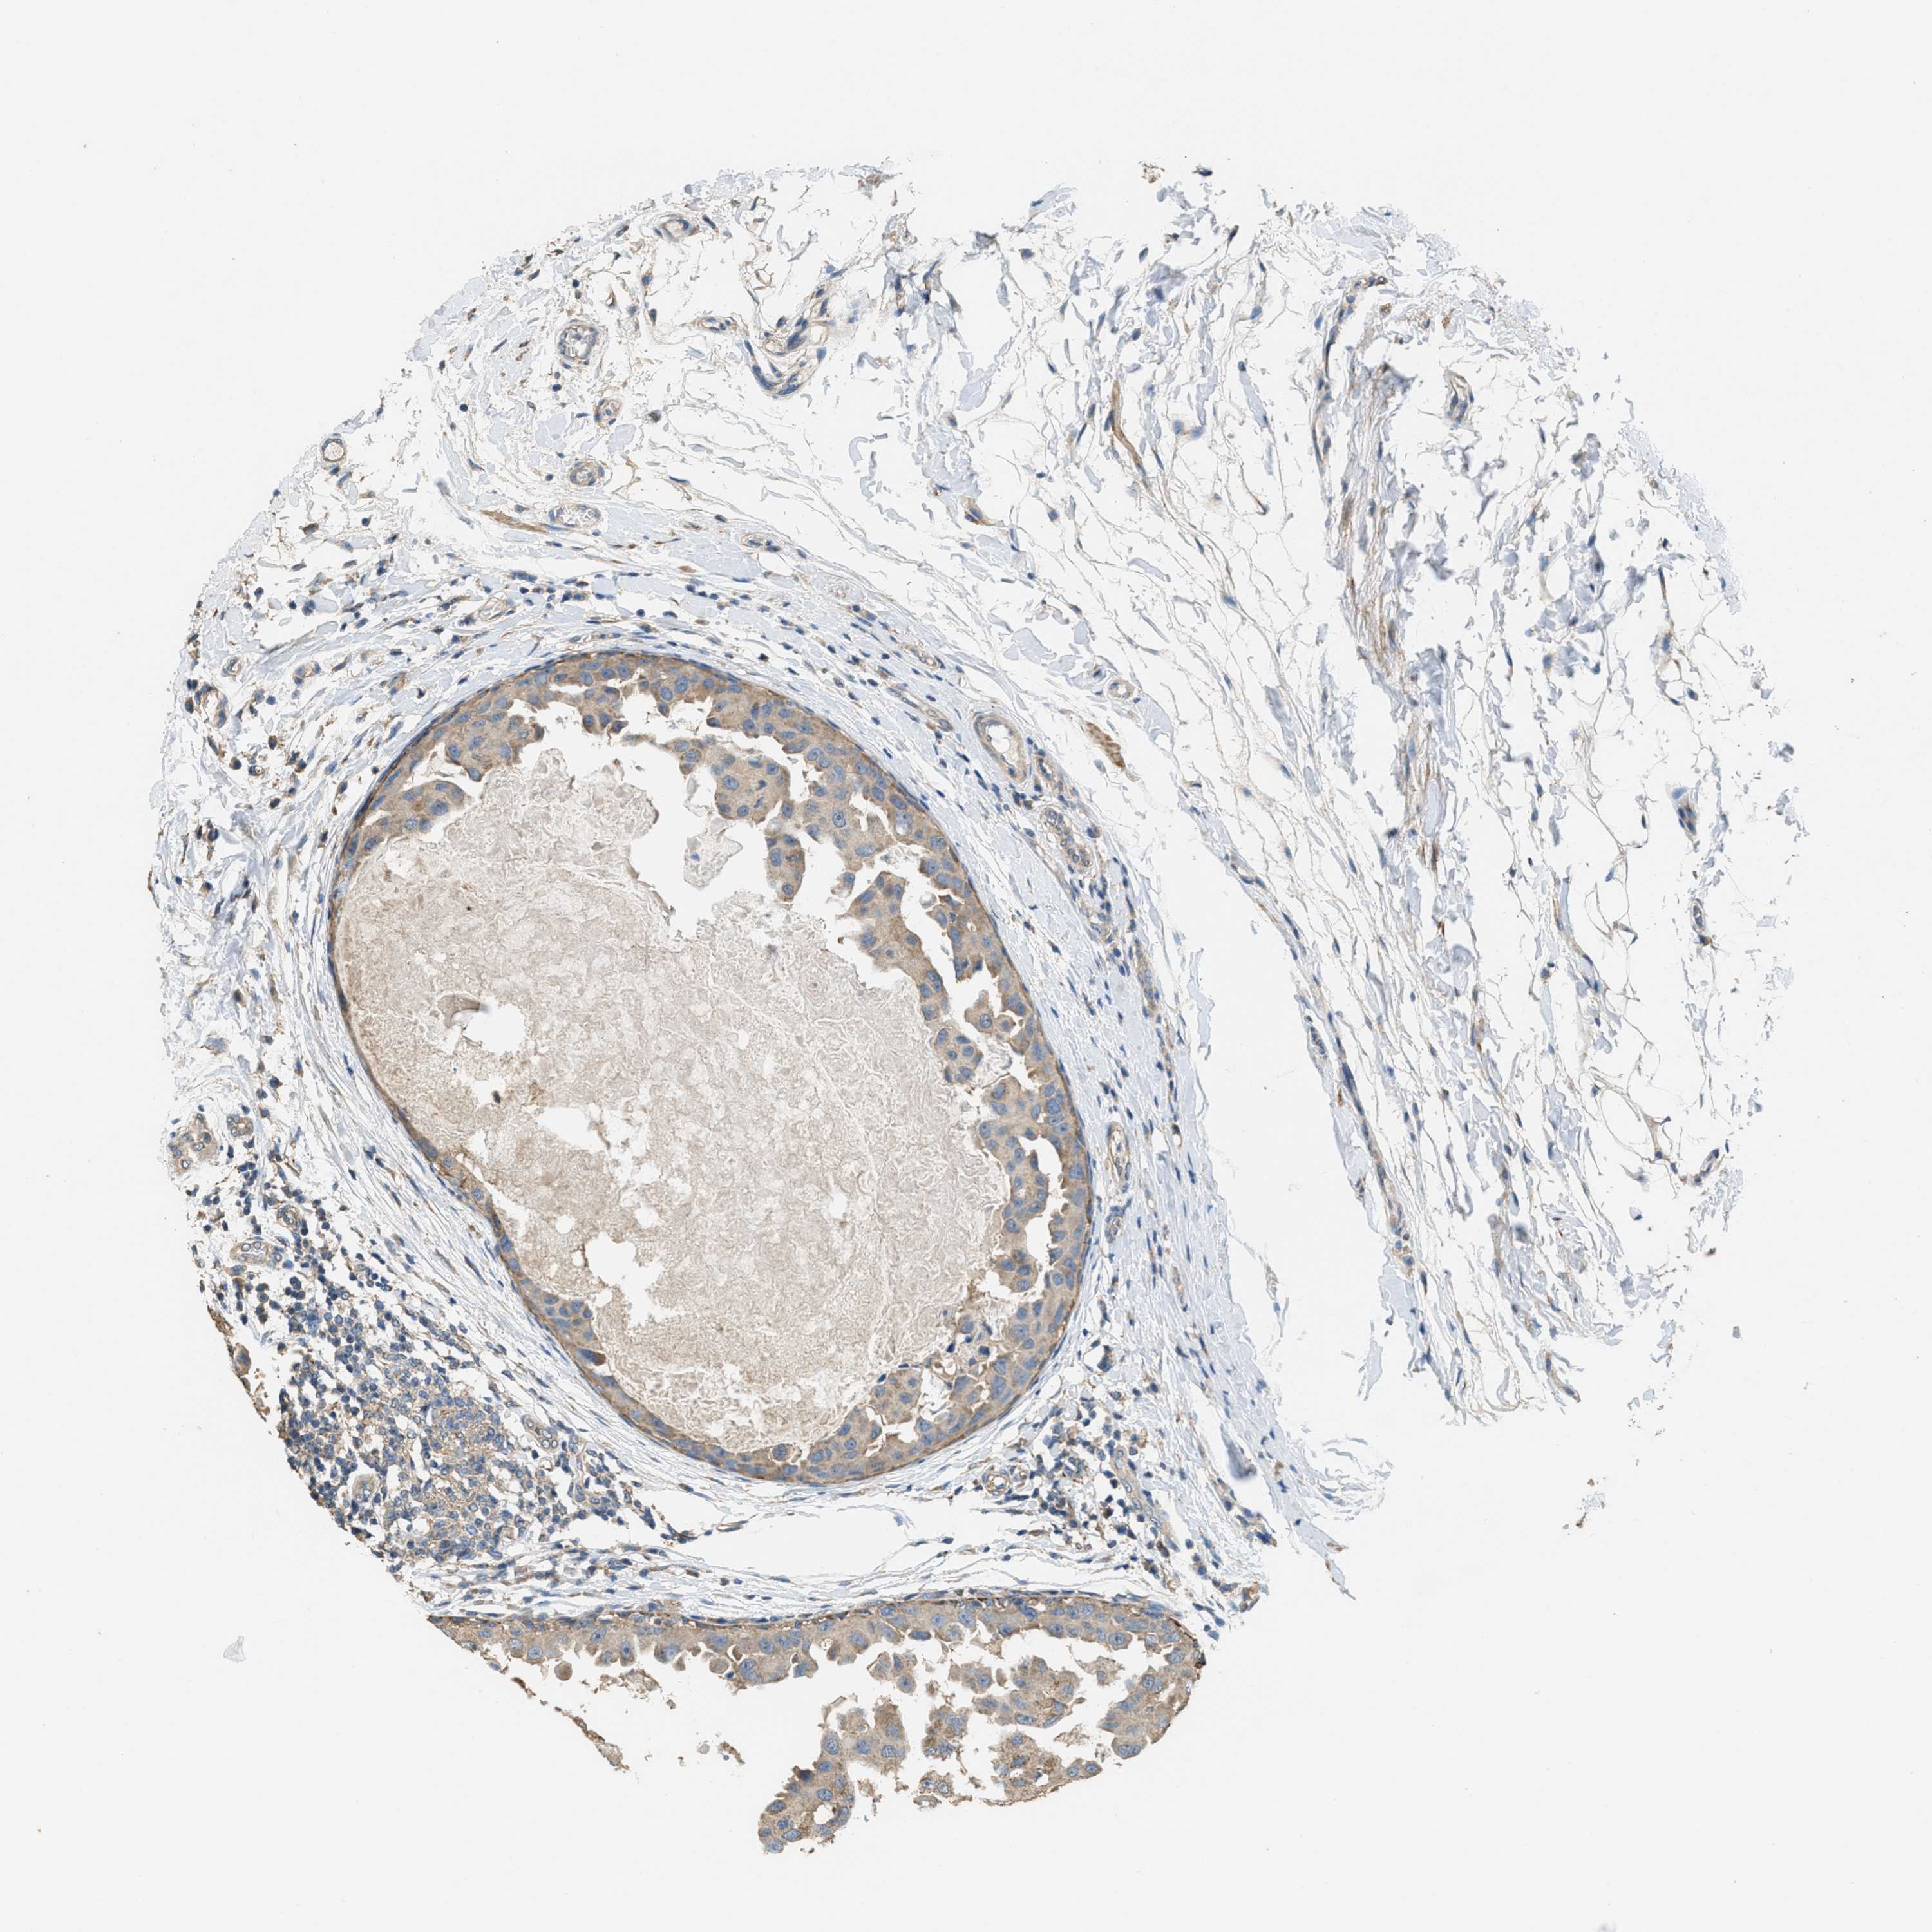

CANCER BREAST CANCER Show tissue menu

BRCA TCGA BRCA VALIDATION PROTEIN EXPRESSION

Breast cancer

Human cancer